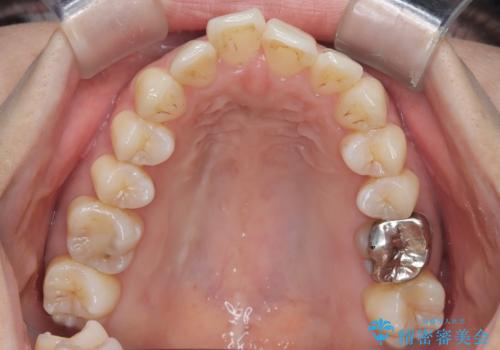

- 患者様は、上顎前歯の突出を改善したいとのご希望で来院されました。診断の結果、噛み合わせや全体的な歯列には大きな問題がないため、上顎のみを対象とした部分矯正が最適と判断しました。特に患者様は短期間での治療完了を希望されていたため、治療期間を約半年と設定しました。審美ワイヤーを用い、前歯を後方に移動させることで、自然で整った仕上がりを目指しました。治療計画は、患者様のスケジュールや希望を最大限考慮し、実現可能な目標を設定しました。